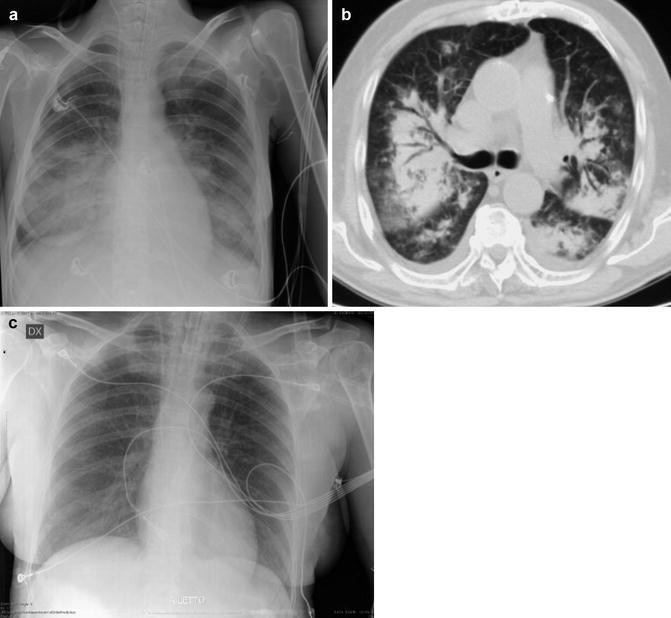

Fig. 1.

Acute complete lower airway obstruction by rapid and severe course of toxic shock syndrome (TSS) in MRSA fatal progressive pneumonia. A 26-year-old menstruating woman with high fever, rash, hypotension, and rapidly evolving multiorgan failure is immediately transferred from ED into the ICU. (a) CXR at the admission in the ICU shows right lower lobe opacity. (b) Follow-up CXR 24 h later shows a new contralateral basal opacity. (c) Bedside longitudinal right LUS shows low right lobe complete consolidation associated to pleural effusion. (d) Patient in extracorporeal membrane oxygenation (ECMO). Twenty-four hours later, follow-up CXR shows completely opacified lungs. (e, f) Unenhanced MDCT axial and coronal MIP reconstructions show bilateral complete lung consolidation associated to pleural effusion. Note hypodense material that fills large airways

Fig. 2.

Acute lower complete airway obstruction in a 16-year-old male with bleeding diathesis by treatment with anticoagulant therapy, abrupt massive postnasal bleeding, and airway hemorrhage by an highly vascularized bleeding nasopharyngeal angiofibroma.(a) CXR after nasogastric tube and right pleural drainages placement shows subtotal opacified lungs. (b) The patient was immediately transferred from ED into the ICU and CXR showed total opacified lungs.(c, d) Emergent unenhanced MDCT coronal reconstructions show hyperdense blood material that fills airways and the bloody hyperdensity mainly in the left lung (compare with Fig. 1). After nasopharyngolaryngoscopy, this patient was treated by emergent preoperative embolization. Juvenile nasopharyngeal angiofibroma is a benign, highly vascular hamartoma that arises from the nasopharynx almost exclusively in adolescent males